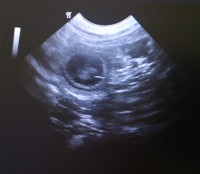

10.06.2022 (23. Trächtigkeitstag) |

Wir waren beim Ultraschall und

Valentina ist tragend!!! Juchuu.

Es sieht alles gut aus und wir konnten viele

Fruchtanlagen sehen. Ich freu mich total.

Wenn alles gut läuft, dann kommen die Kleinen so

um den 18. Juli herum zur Welt

Ich messe

ja immer gerne den Bauchumfang vom Ultraschall

an. Und wir starten mit 65

cm